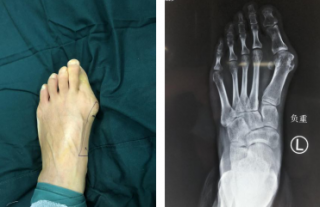

踇趾外翻畸形疼痛大半年,仁慈足踝科微创踇外翻技术30分钟完成矫形

说起踇趾外翻,很多人不陌生,就是踇趾骨和第一跖骨之间关节倾斜超过15度,造成红肿和疼痛,严重时甚至不能走路。踇趾

详细 >>